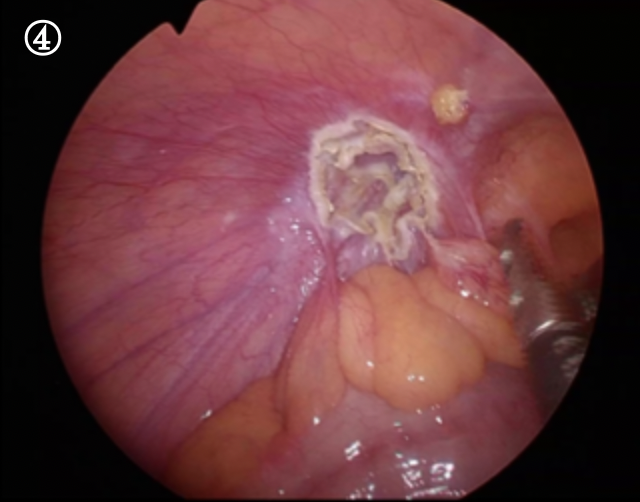

ソケイヘルニアをおなかの内側から見た写真です。ソケイ部に開いた大きな穴におなかの中の脂肪や腸が入り込んでいます。

まずはこれを引き出すことから始まります。これを引き出すと・・・・・

ぽっかりと大きなトンネルが見えます。これがヘルニア門と言われる穴です。腸の一部はこの門の奥に癒着し、完全には引き出すことが出来ませんでした